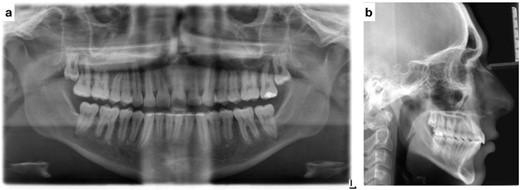

Lateral cephalometric radiograph analysis showed a mild mandibular deficiency and high mandibular plane angle, retroclined maxillary incisors and proclined mandibular incisors (Fig. 3b). Panoramic radiography showed impacted third molars; rocky mountain analysis on the posterior-anterior cephalometric radiograph showed a narrow maxilla in the transverse dimension (Fig. 3c).

(a) Pretreatment panoramic radiograph; (b) pretreatment lateral cephalometric radiograph; (c) pretreatment posterior-anterior cephalometric radiograph.